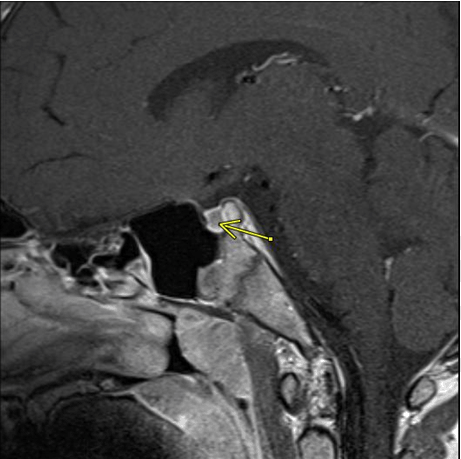

Presentation was concerning for Cushing syndrome and 1 mg overnight dexamethasone suppression test was performed with AM cortisol 2.0 mcg/dL and ACTH 15 pg/mL. Despite the indeterminate results, over a 3 month period he gained an additional 4.1 kg without height gain and appeared more Cushingoid. A 48- hour low dose dexamethasone suppression test was performed; baseline 8 am cortisol was 22.1 mcg/dL, 48- hour cortisol was 5.8 mcg/dL, and ACTH was 29 pg/ mL. With biochemical evidence of Cushing disease, MRI of the brain was performed revealing a heterogeneous filling defect within the left and right lateral aspects of the pituitary. A microadenoma was not visualized, but could not be excluded (Figure 1), (Figure 2).

Figure 2: Left sagittal image of MRI with contrast of the heterogeneous filling defect with possible adenoma highlighted by arrow.